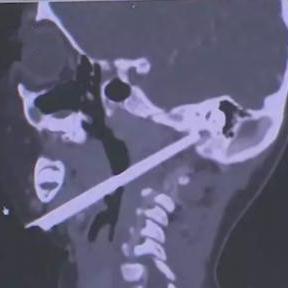

这名男子遭遇了一场意外,一根筷子从外耳道上方刺入,直接穿透颅底抵达鼻咽部,这看似普通的筷子,此时却成了一颗致命的定时炸弹,筷子的尖端距离颈内动脉仅5毫米,颈内动脉是大脑供血的主要血管之一,一旦受损,大出血将瞬间发生,患者的生命将危在旦夕,这次异物恰好避开了重要血管,只能说是“不幸中的万幸”,但手术取出筷子的过程依旧充满了巨大的风险。

接到患者后,珠江医院创伤中心迅速启动了严重创伤救治“绿色通道”,耳鼻咽喉头颈外科、神经外科、影像诊断科、麻醉科等多个科室的专家迅速集结,展开了多学科会诊(MDT),通过先进的CT血管成像技术,专家们精准地确定了筷子的位置以及它与周围血管的关系。